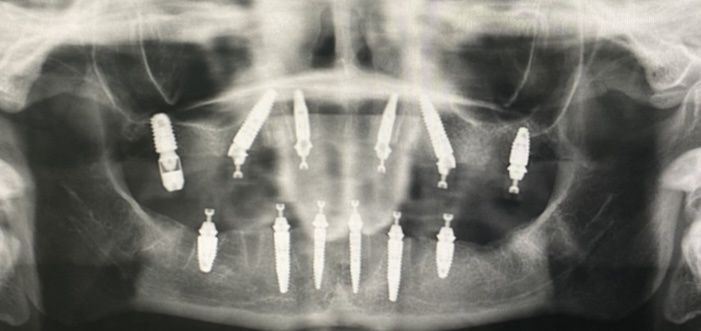

За время операции я два раза просыпалась, анастезиолог подкручивал колесико на капельнице и меня снова накрывал сон - сейчас я точно знаю, что при правильной и качественной процедуре седации такого быть не должно. Окончательно меня разбудили где-то к 17ти часам, хирургическая часть была закончена - ИФ удалил остатки моих зубов, два старых импланта (давно беспокоящий меня имплант шестерки и имплант центрального резца, который был бесполезен для планируемой конструкции), оставил один единственный имплант в позиции верхней семерки и установил еще одиннадцать имплантов марки Штрауманн.

Итог хирургического этапа. Снимок мой.